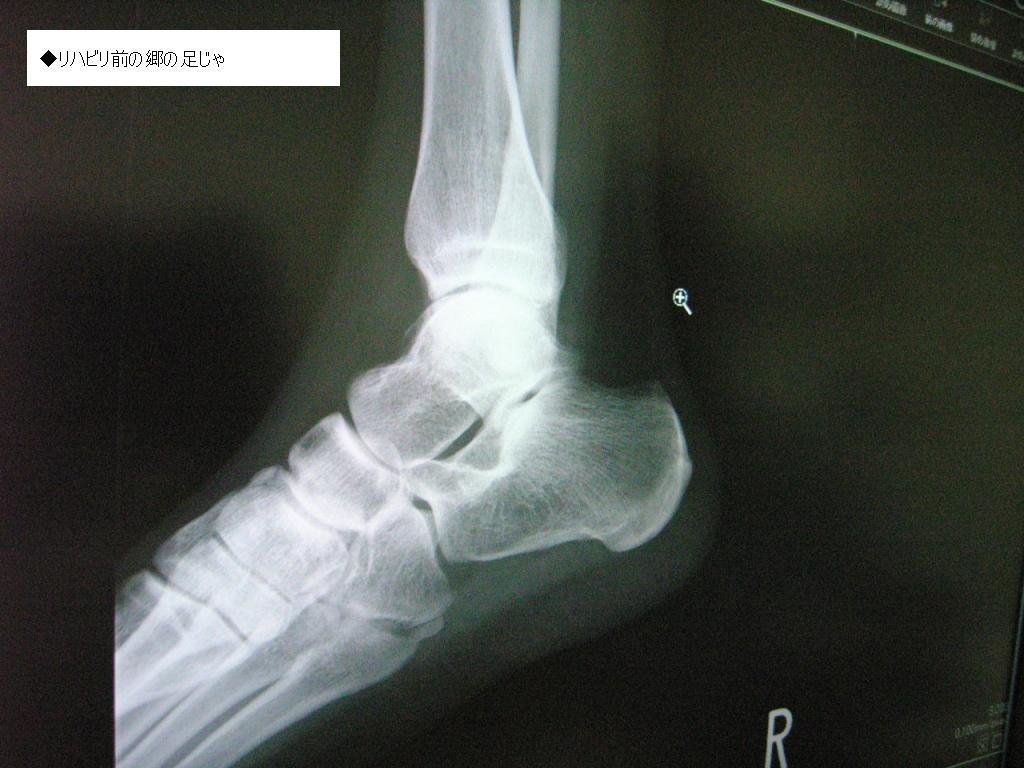

◆無くなった郷の軟骨っ♪

レントゲンを速攻で撮影し、再び診断室へ郷w

先生様『骨が・・・無くなってる。以前骨折ったことある?』

先生様『ほらここ、右足首クルブシの下スッポリ溶けてるね』

ガビーン _│ ̄│○ 郷の骨がお肉に変化じゃ

ショックに追い討ちをかけるように、足首の左右にある間接の隙間が殆んど無い状態であることを告げられる。